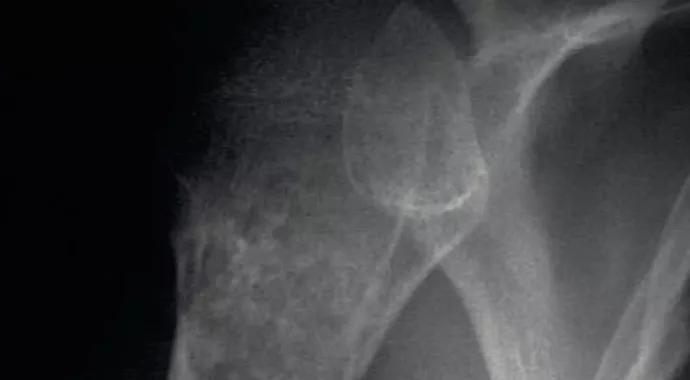

Figure 2. Anteroposterior radiograph showing an enchondroma of the proximal humerus. The calcification pattern largely resembles the “popcorn” appearance of the typical benign enchondromatous lesion.

Figure 3. Radiograph showing a chondroid tumor in the proximal humerus with endosteal scalloping, cortical destruction, periostitis and calcifications consistent with chondrosarcoma.